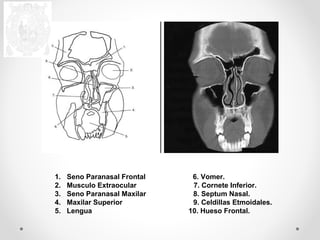

1. Seno Paranasal Frontal 6. Vomer.

2. Musculo Extraocular 7. Cornete Inferior.

3. Seno Paranasal Maxilar 8. Septum Nasal.

4. Maxilar Superior 9. Celdillas Etmoidales.

5. Lengua 10. Hueso Frontal.